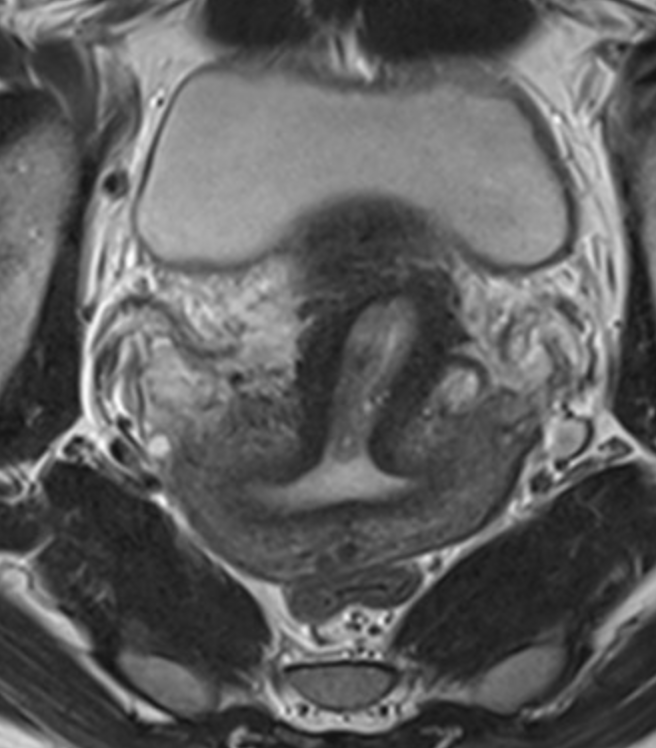

Junctional zone

• Arrow head = endometrium

• Middle arrow = junctional zone

• Long arrow = Outer myometrium